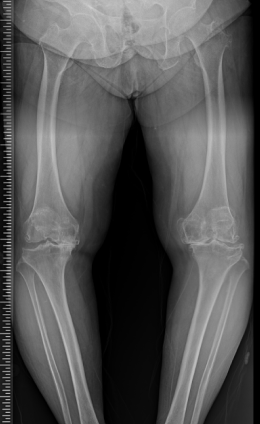

수술 전후 사례

수술 전

-

수술 후